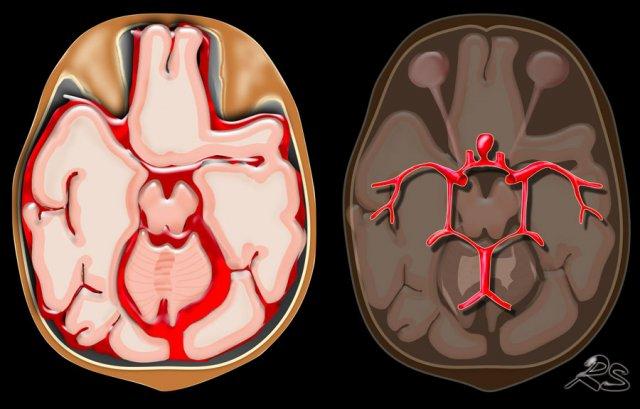

Dưới nhện

Xuất huyết dưới nhện (SAH) là chảy máu vào khoang dưới nhện giữa màng nhện và màng mềm.

Nguyên nhân phổ biến nhất là chấn thương.

SAH không do chấn thương thường là hậu quả của vỡ phình động mạch với máu lan vào các bể dưới nhện (hình).

Phương thức chẩn đoán hình ảnh được lựa chọn đầu tiên ở bệnh nhân nghi ngờ SAH trên lâm sàng là chụp CT không tiêm thuốc cản quang (NECT).

NECT dương tính với SAH trong 98% trường hợp trong vòng 12 giờ kể từ khi khởi phát.

Nếu nghi ngờ cao nhưng CT âm tính, chọc dò tủy sống được thực hiện để phát hiện máu trong dịch não tủy.

Các hình ảnh cho thấy xuất huyết dưới nhện do vỡ phình động mạch não giữa bên trái (mũi tên).

Xuất huyết dưới nhện được thảo luận chi tiết hơn tại đây.

Xuất huyết dưới nhện

Vỡ phình động mạch

Như đã đề cập, xuất huyết dưới nhện (SAH) là tình trạng chảy máu vào khoang dưới nhện, nằm giữa màng nhện và màng nuôi.

SAH không do chấn thương là hậu quả của vỡ phình động mạch, với máu lan vào các bể dịch não tủy dưới nhện (hình).

Hình ảnh CT của bệnh nhân SAH tự phát.

CTA được thực hiện để tìm kiếm phình động mạch.

Tiếp tục với DSA…

Lưu ý có hai túi phình động mạch (mũi tên):

- Xoang cảnh (carotid siphon)

- Động mạch não giữa

Cả hai đều được điều trị bằng can thiệp nút coil.